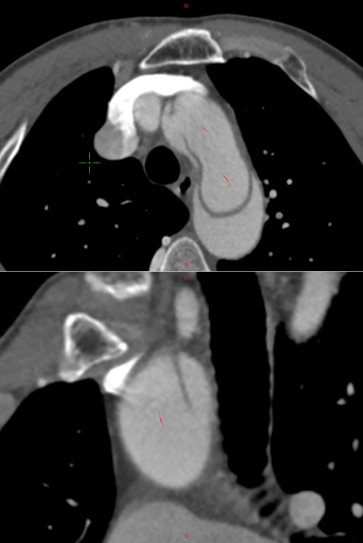

术后12个月CT血管造影(CTA)随访显示,支架移植物位置稳定,无明显移位或变形,分支血管通畅。

First-In-HuMan study--CTA

CTA preoperation

CTA 12 monthes FU